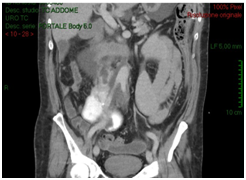

A 54-years old Caucasian man affected by sub renal aortic aneurysm, undertake vascular surgery of aortotomy and bilateral aortoiliac Dacron prosthesis implantation. Patient had a good health status; he had hypertension (with good control of blood pressure), diabetes mellitus type 2. He had no operations. In the past. In 5 post-operative days, due to post-operative anaemia, fever and slight increased creatinine (around 1.3 mg/dl), the patient received an ultrasound scan that showed intra-retroperitoneal fluid without any sign of hydronephrosis. In the suspect of haemorrhage, vascular surgeons performed an abdomen CT-scan with contrast that reported organized hematoma along the right iliac branch associated to intraperitoneal serous-hematic fluid (Figure 1). CT-scan did not have delayed phases. In XII post-operative day, patient was transferred to intensive care ward because of fever until 39°C, dynamic ileus and uremic status. He received an abdomen contrast CT-scan that showed increasing of intra-retroperitoneal fluid with small bowel and right colon compression and increase of right iliac region serous-hematic fluid (Figure 2).

Figure 1: Abdomen CT-scan with contrast that reported organized hematoma along the right iliac branch associated to intraperitoneal serous-hematic fluid.